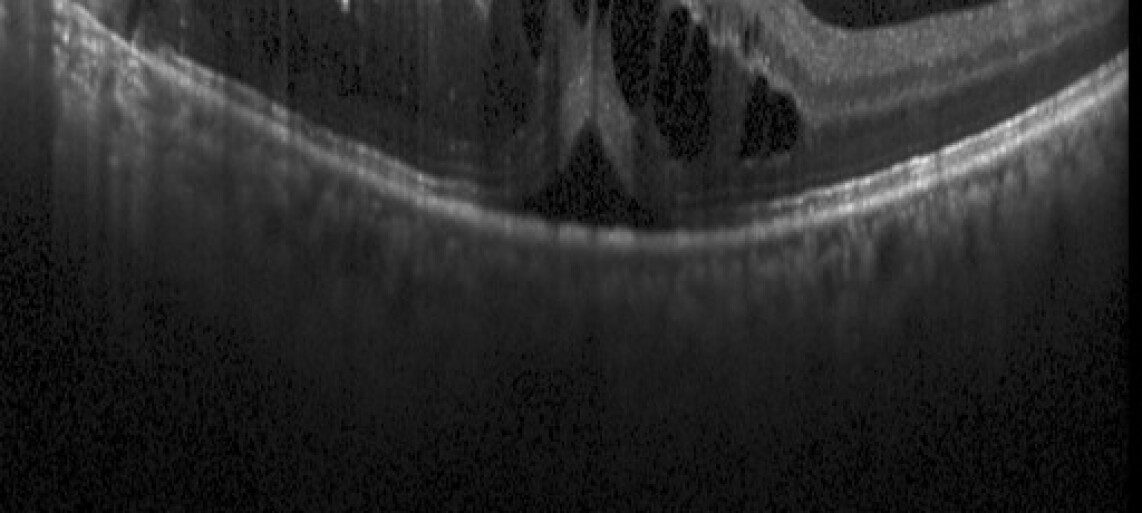

As shown by the green flow on the right side of visual modules in Fig. 3, we adopt the pretrained model Zhou et al. (2020) for layer segmentation and enhance it with anomaly-discriminative representations, derived from the absolute difference between the original input and its healthy counterpart generated by GANomaly, from Yang et al. (2024). These inputs are denoted as and respectively. Although pretrained models introduce noise and artifacts, they still offer valuable guidance by capturing the positional relationships between lesions and retinal layers and identifying anomalous regions. As illustrated in Fig. 4 (b, d), their outputs are imperfect yet effectively highlight where lesions occur in relation to specific retinal layers, providing critical insights for accurate lesion localization.